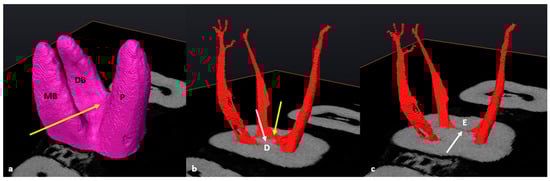

3.1. Mandibular First Molars: Two Rooted

3.2. Mandibular First Molars: Three Rooted

3.3. Maxillary First Molars: Three Separate Roots

3.4. Maxillary Molars: Variants in Mesial or Distal Bifurcations